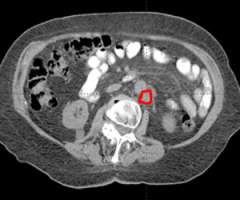

The second row shows images (axial, coronal, and sagittal) of the distribution of the radiation dose that was delivered to this area. One can see that the dose of radiation to this target is very tightly distributed to avoid as much normal tissue as possible.

SBRT requires highly accurate, precise, and focused radiation delivery in order to be successful because of the high dose of the treatment and the rapid radiation dose drop-off. It utilizes the same principles that have allowed radiation oncologists and neurosurgeons to successfully deliver highly focused and precise radiation treatment to brain tumors and brain metastases. Unlike the CNS, however, tumors and organs throughout the body can potentially move with breathing and other factors. SBRT treatments require accurate and precise tumor localization at the time of radiation simulation (Figure 4). Our expert team works closely with our interventional radiologists or surgeons to place fiducials (tiny gold seeds, or coils) into a patient's tumor in as minimally invasive a way as possible. These fiducials act as localizing and tracking devices (Figure 5). Fiducials assist us in targeting the tumor more accurately and precisely. The placement of fiducials is a procedure much like obtaining a biopsy for the tissue diagnosis of the cancer and is safely performed under image-guidance.